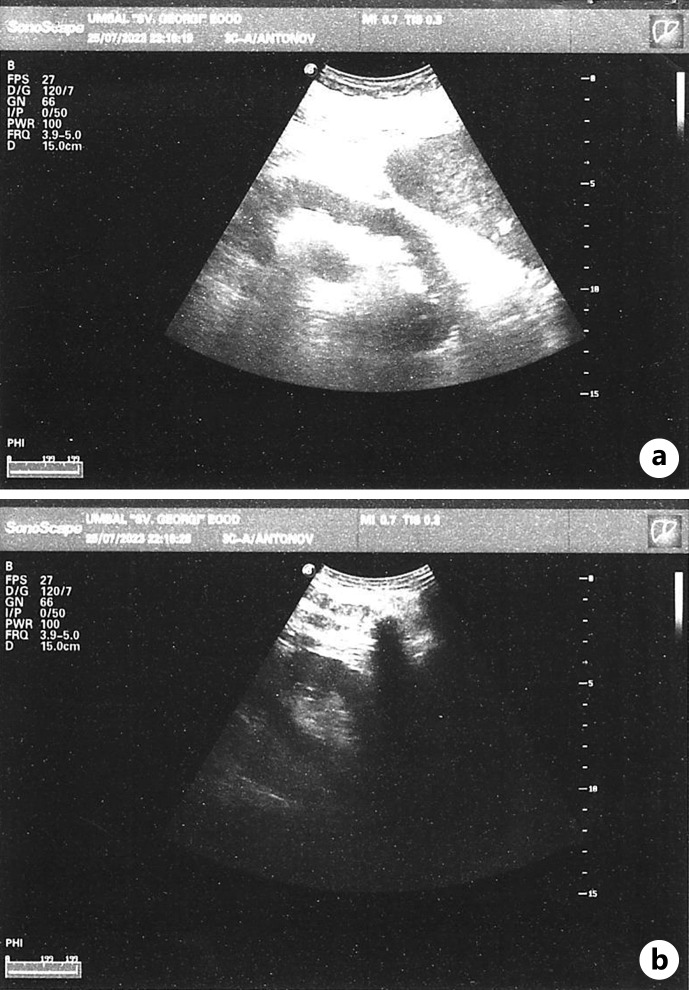

导言:气肿性肾盂肾炎是一种罕见但可能危及生命的尿路感染,其特点是在肾实质、集合系统和肾周组织中形成气体。这种疾病通常发生在有特定易感因素的患者身上,如糖尿病、先天性或后天性梗阻性尿路病或服用免疫抑制剂的患者。在极少数情况下,有其他易感因素(如使用 SGLT2 抑制剂)的患者也会发病,但这种情况并不常见。与使用 SGLT2 抑制剂相关的尿路感染发生率仍有待商榷,但医学文献中已描述了与 SGLT2 抑制剂相关的气肿性肾盂肾炎病例:病例介绍:我们介绍了一例罕见的气肿性肾盂肾炎患者,该患者服用 SGLT2 抑制剂,但没有该病的典型危险因素:尽管使用 SGLT2 抑制剂后发生尿路感染的频率相对较低,但其广泛应用于治疗多种具有重大社会意义的疾病,强调了专科医生有必要了解与使用该药物相关的所有潜在风险,包括发生严重尿路感染的风险。

Introduction: Emphysematous pyelonephritis is a rare but potentially life-threatening urinary tract infection characterized by the formation of gas in the renal parenchyma, collecting system, and perinephric tissue. The condition typically develops in patients with specific predisposing factors such as diabetes mellitus, congenital or acquired obstructive uropathies, or individuals taking immunosuppressive agents. Rarely can the disease occur in patients with other predisposing factors, such as the use of SGLT2 inhibitors, but this is quite uncommon. The incidence of urinary tract infections associated with their use is still debatable, but cases of emphysematous pyelonephritis associated with SGLT2 inhibitors have been described in medical literature.

Case presentation: We present a rare case of a patient with emphysematous pyelonephritis without classical risk factors for the disease, who was taking an SGLT2 inhibitor.